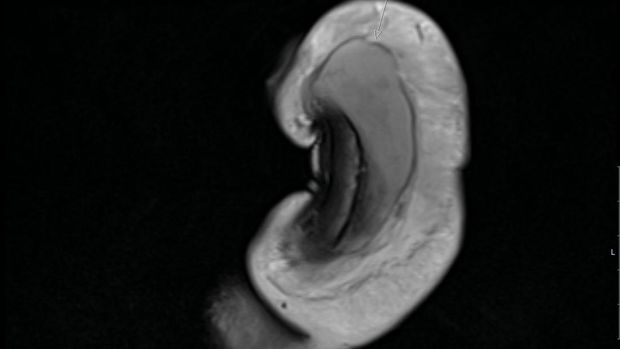

Setelah diperiksa, dokter bedah menemukan adanya patahan vertikal sepanjang 3 cm di penis, yang dikonfirmasi pemeriksaan MRI. Pakar urologi yang menangani kasus itu mengisahkan, luka yang dialami pasien tidak mereka temui pada pengidap lainnya.

penis patah Foto: British Medical Journal (BMJ) |